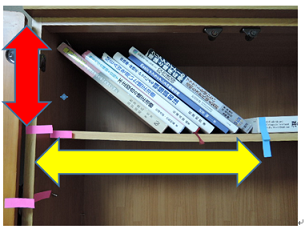

MEAW(マルチループ)を利用して歯を動かす隙間の作り方は2種類あります。

②ふたつ目は以下の様な原理です。

MEAW(マルチループ)を利用して歯を動かす隙間の作り方は2種類あります。

①ひとつ目は以下の様な原理です。

これを身近な7冊の本を使って説明していきましょう。